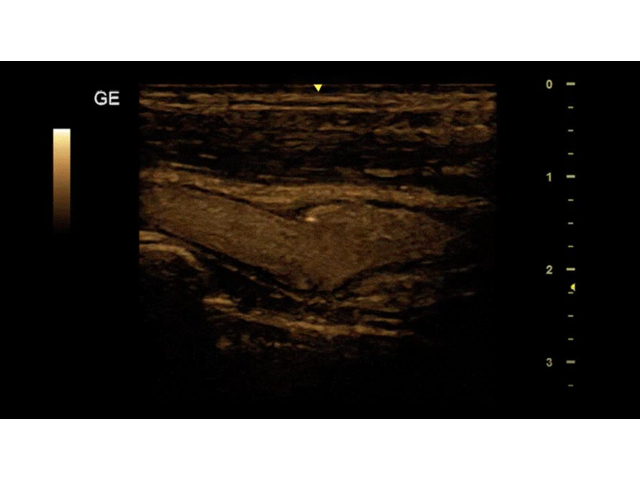

Ультразвуковой сканер GE Versana Essential отличается высокой точностью и мобильностью. Он широко используется при обследовании скелетно-мышечной системы и является незаменимым инструментом в урологии, гинекологии, педиатрии и общей радиологии.

Благодаря передовым технологиям и инновационным функциям, ультразвуковой сканер GE Versana Essential обеспечивает высокую четкость и детализацию получаемых изображений. Он позволяет врачам проводить диагностику и оценку состояния тканей и органов с высокой точностью, что способствует более точным и эффективным клиническим решениям.

• На лицевой панели устройства имеются три разъема для датчиков, позволяющих работать с различными типами допплеровского изображения, включая импульсно-волновой, энергетический и цветной доплер.